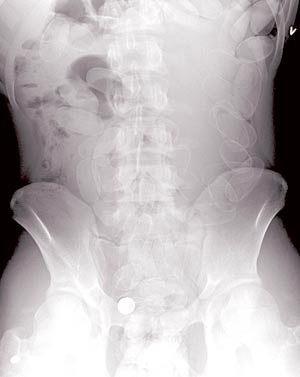

Pasient 1. 33 år gammel mann som kom med fly fra Sør-Europa til Skandinavia. Han ble pågrepet av politiet og brakt til oss fordi det var mistanke om narkotikasmugling. Politiet anmodet om medisinsk undersøkelse. Pasienten bekreftet inntak av 68 pakker med ukjent stoff ca. 30 timer før ankomst i sykehuset. Han samtykket til klinisk undersøkelse, som var upåfallende – blodtrykk 124/82 mm Hg, puls 62/min, temperatur 36,7 °C. Røntgen oversikt abdomen innleggelsesdagen viste flere pakker ca. 2 x 4,5 cm i hovedsakelig øvre del av gastrointestinaltractus. Pasienten fikk høydose laktulose 20 ml x 6 og amidotrizoinsyre (Gastrografin) 100 ml per os. Han kastet opp to pakker innleggelsesdagen og kvitterte deretter fortløpende ut nye pakker med avføringen. Nye røntgenbilder viste at pakkene flyttet seg langsomt lenger distalt i gastrointestinaltractus, og pasienten fikk dagene etter ytterligere doser med laktulose 40 ml x6 og amidotrizoinsyre 30 ml per os. Enkelte røntgenbilder viste luft-væske-speil, men pasienten var hele tiden uten smerter og bløt i buken ved undersøkelse, uten klinisk mistanke om ileusutvikling. Han utviklet heller ikke symptomer på intoksikasjon. Pasienten ble utskrevet til politiets varetekt etter fire døgn da alle pakkene var kommet ukomplisert ut (fig 1). Ifølge narkotikaseksjonen ved Oslo politidistrikt inneholdt hver pakke kokain med en antatt markedsverdi på ca. 10 000 – 15 000 kroner (personlig meddelelse fra narkotikaseksjonen).

Pasient 3. 19 år gammel mann ble brakt til Ullevål universitetssykehus av politiet med mistanke om narkotikasmugling. Han nektet klinisk undersøkelse, men godtok radiologiske undersøkelser. Røntgen oversikt abdomen viste mer enn 40 pakker ca. 2x 4 cm (fig 3). Han fikk natriumfosfat (Phosphoral) og laktulose, og neste døgn kom det ukomplisert ut ca. 60 pakker med avføringen.